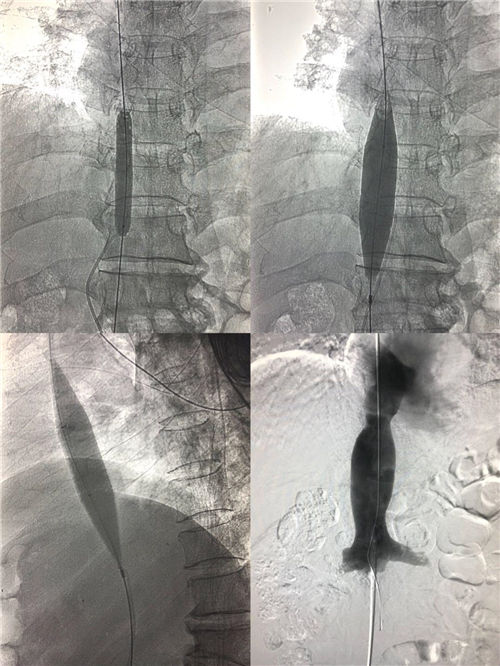

8月31日早8:15,介入科李建国主任、何彤副主任在局麻下对患者实施了经右侧颈静脉、右侧股静脉上下入路穿刺,对端造影,利用导管导丝成功打通下腔静脉闭塞段。再选用不同型号球囊分次扩张,在全体医护人员的密切协作努力下,闭塞的下腔静脉终于通畅,手术历时1小时15分钟,患者生命体征平稳安返病房,进一步的康复中。

布-加综合征首选介入手术治疗,该手术是介入医生在DSA的透视监视下利用穿刺针、导管导丝、球囊等一系列器材对患者进行的微创治疗,手术能迅速打通下腔静脉闭塞段,显著降低下腔静脉回流右心房的阻力,可有效减少食管胃底静脉曲张再出血和腹水复发等肝硬化并发症,使患者下肢溃烂得到逐步改善。手术时间短,不需开刀,患者全程清醒无痛苦,创伤小、效果好,能为此类患者快速有效解除病痛折磨。